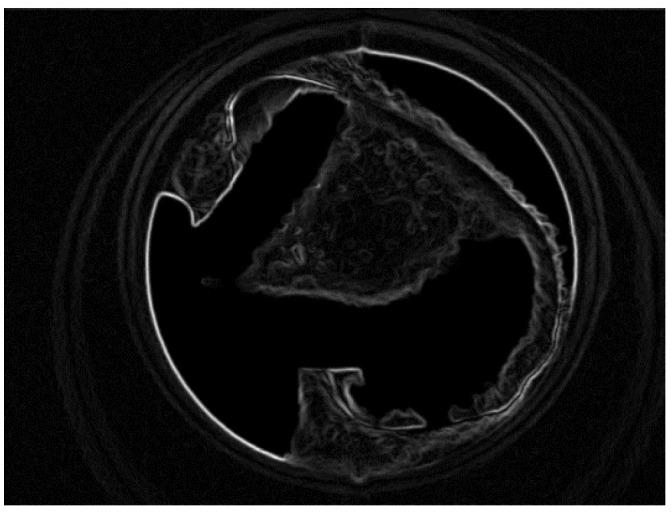

Oral mucosal lesions (OML) and oral potentially malignant disorders (OPMDs) have been identified as having the potential to transform into oral squamous cell carcinoma (OSCC). This research focuses on the human-in-the-loop-system named Healthcare Professionals in the Loop (HPIL) to support diagnosis through an advanced machine learning procedure. HPIL is a novel system approach based on the textural pattern of OML and OPMDs (anomalous regions) to differentiate them from standard regions of the oral cavity by using autofluorescence imaging. An innovative method based on pre-processing, e.g., the Deriche-Canny edge detector and circular Hough transform (CHT); a post-processing textural analysis approach using the gray-level co-occurrence matrix (GLCM); and a feature selection algorithm (linear discriminant analysis (LDA)), followed by k-nearest neighbor (KNN) to classify OPMDs and the standard region, is proposed in this paper. The accuracy, sensitivity, and specificity in differentiating between standard and anomalous regions of the oral cavity are 83%, 85%, and 84%, respectively. The performance evaluation was plotted through the receiver operating characteristics of periodontist diagnosis with the HPIL system and without the system. This method of classifying OML and OPMD areas may help the dental specialist to identify anomalous regions for performing their biopsies more efficiently to predict the histological diagnosis of epithelial dysplasia.

口腔黏膜病变(OML)和口腔潜在恶性疾病(OPMDs)已被确定为有可能转化为口腔鳞状细胞癌(OSCC)。本研究专注于一种名为医疗保健专业人员参与的人机交互系统(HPIL),通过先进的机器学习程序支持诊断。HPIL 是一种基于 OML 和 OPMDs(异常区域)纹理模式的新型系统方法,通过自发荧光成像将其与口腔标准区域区分开来。本文提出了一种基于预处理(例如 Deriche-Canny 边缘检测和圆形霍夫变换(CHT))、使用灰度共生矩阵(GLCM)进行纹理分析的后处理方法以及特征选择算法(线性判别分析(LDA))的创新方法,然后是 k-最近邻(KNN)来对 OPMD 和标准区域进行分类。在区分口腔标准和异常区域方面,准确性、灵敏度和特异性分别为 83%、85%和 84%。通过牙周病医生使用 HPIL 系统和不使用系统进行诊断的接收器工作特性来绘制性能评估。这种分类 OML 和 OPMD 区域的方法可能有助于牙科专家识别异常区域,以便更有效地进行活检,从而预测上皮发育不良的组织学诊断。